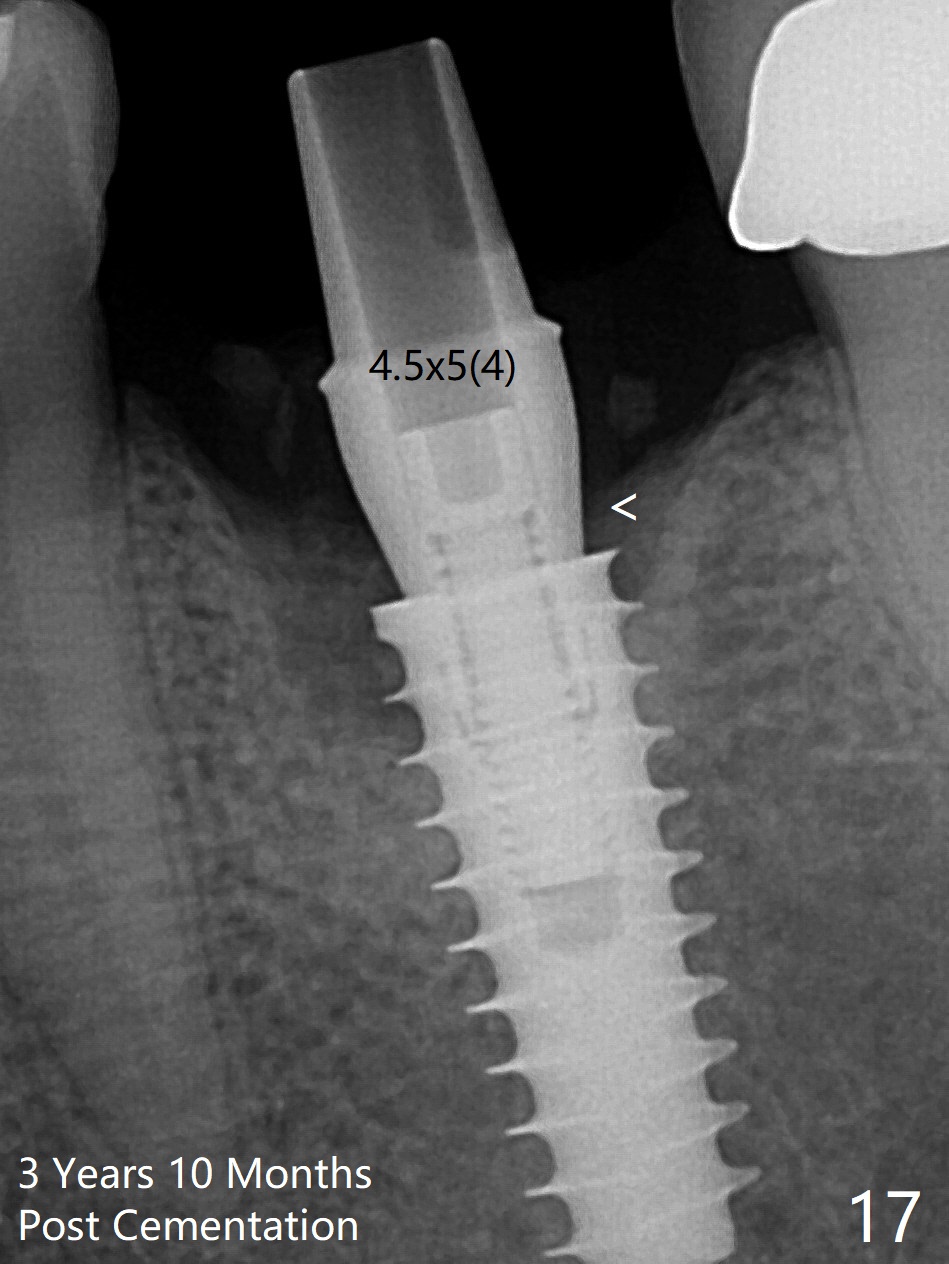

The gingiva looks healthy 8 months postop (3 months post cementation (after abutment screw retightening and addition of porcelain to proximal surfaces, Fig.12). New bone has apparently covered the implant plateau (Fig.13 arrows). Bone density between threads increases 9 months post cementation (Fig.14). There is 2 mm bone superior to the implant plateau mesial and distal 1 year 9 months post cementation (Fig.15,16). The crown/abutment is loose 3 times (3 months (Fig.14), 11 months (between Fig.14 and 15) and 2 years 3 months post cementation). In spite of being stable 3 years 10 months post cementation, a smaller abutment is placed (Fig.17 (PA), 18 (BW)) with impression for a new crown. After intraoral cementation, the new crown/abutment is removed for residual cement removal. When the complex is reseated, it is not smooth, probably due to proximal undercut. Fortunately the abutment appears to be completely seated, followed by 20 Ncm torque (Fig.19).